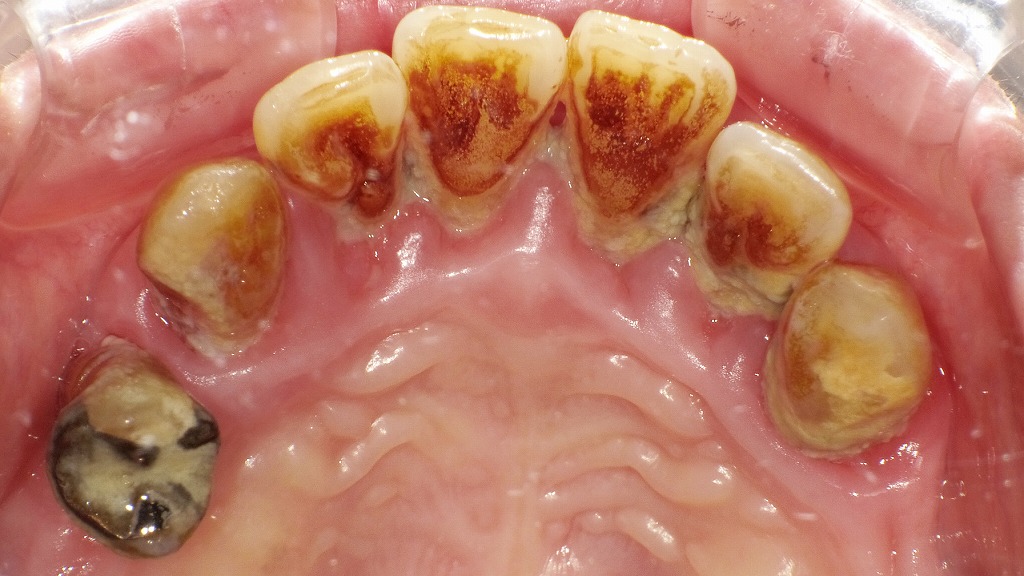

赤矢印で示す部分では、歯を支える歯槽骨が大きく吸収され、歯ぐきが下がり歯の根が露出しています。これは重度歯周病にみられる典型的な所見で、炎症が長期間続いた結果、歯周組織が破壊された状態です。ここまで進行すると歯の動揺が強くなり、最終的には抜歯が必要となる場合もあります。早期発見・早期治療が歯を守るために重要です。

歯を支える骨(歯槽骨)が溶けて減っていく現象を「アタッチメントロス」と呼びます。

歯周ポケットの深さやレントゲン画像から確認され、歯周病が進行している指標となります。

45歳~54歳の年齢層では、糖尿病患者のアタッチメントロスは約5mmと、健常者に比べて明らかに進行しています。

糖尿病が歯周病の進行を早め、歯を支える組織を著しく破壊していることがわかります。